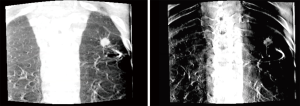

Tomosynthesis involves serial X-ray images taken in during movement of a c-arm through limited angles (usually −20 to +20 or −35 to +35 degrees). Images can be viewed individually to eliminate overlapping structures or stacked together to form a 3D model. There are a variety of reconstruction algorithms that are used to create an additive effect to make smaller lesions more visible and in sharper focus while blurring out of plane images (Figure 2). Nelson et al. showed that the use of tomosynthesis in combination with ENB in an animal model could help to eliminate the CT-to-body divergence issue that hinders ENB alone (7). Additionally, the tomosynthesis images were able to resolve 7 mm lesions that were not visible on standard fluoroscopy. The results of this study showed a significant correlation (coefficient 0.926) in position as measured with tomosynthesis compared to high resolution CT scan (HRCT). Conversely with ENB alone, there was significant divergence between the perceived distance to the target and the actual distance as measured by HRCT (correlation coefficient 0.048, P<0.0001).